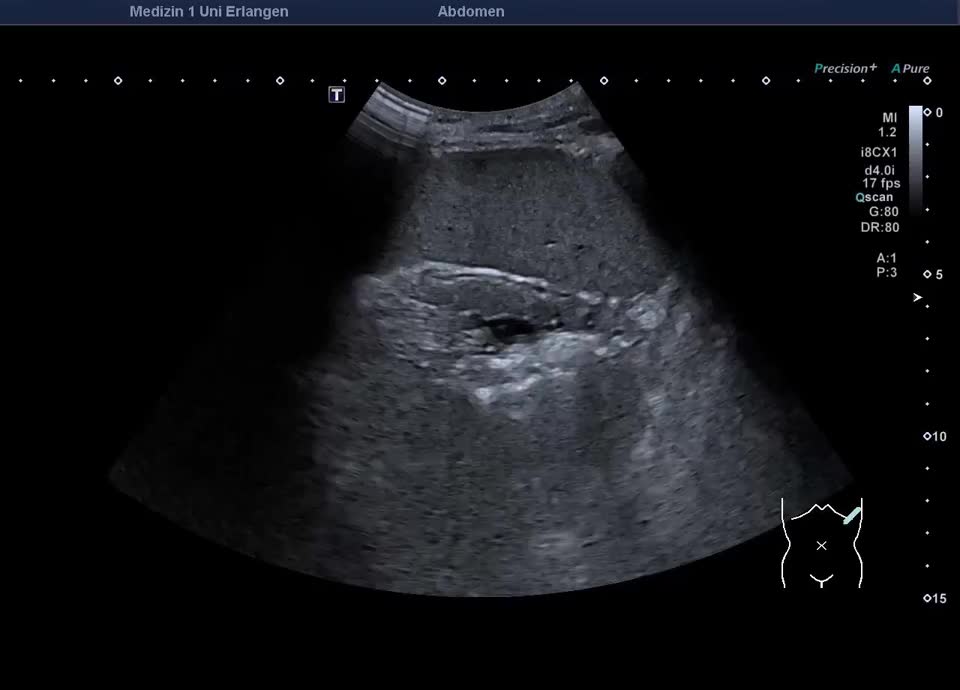

Cruveilhier-Baumgarten-Syndrom: rekanalisierte Umbilikalvene bei Leberzirrhose (hochfrequenter Linearschallkopf)